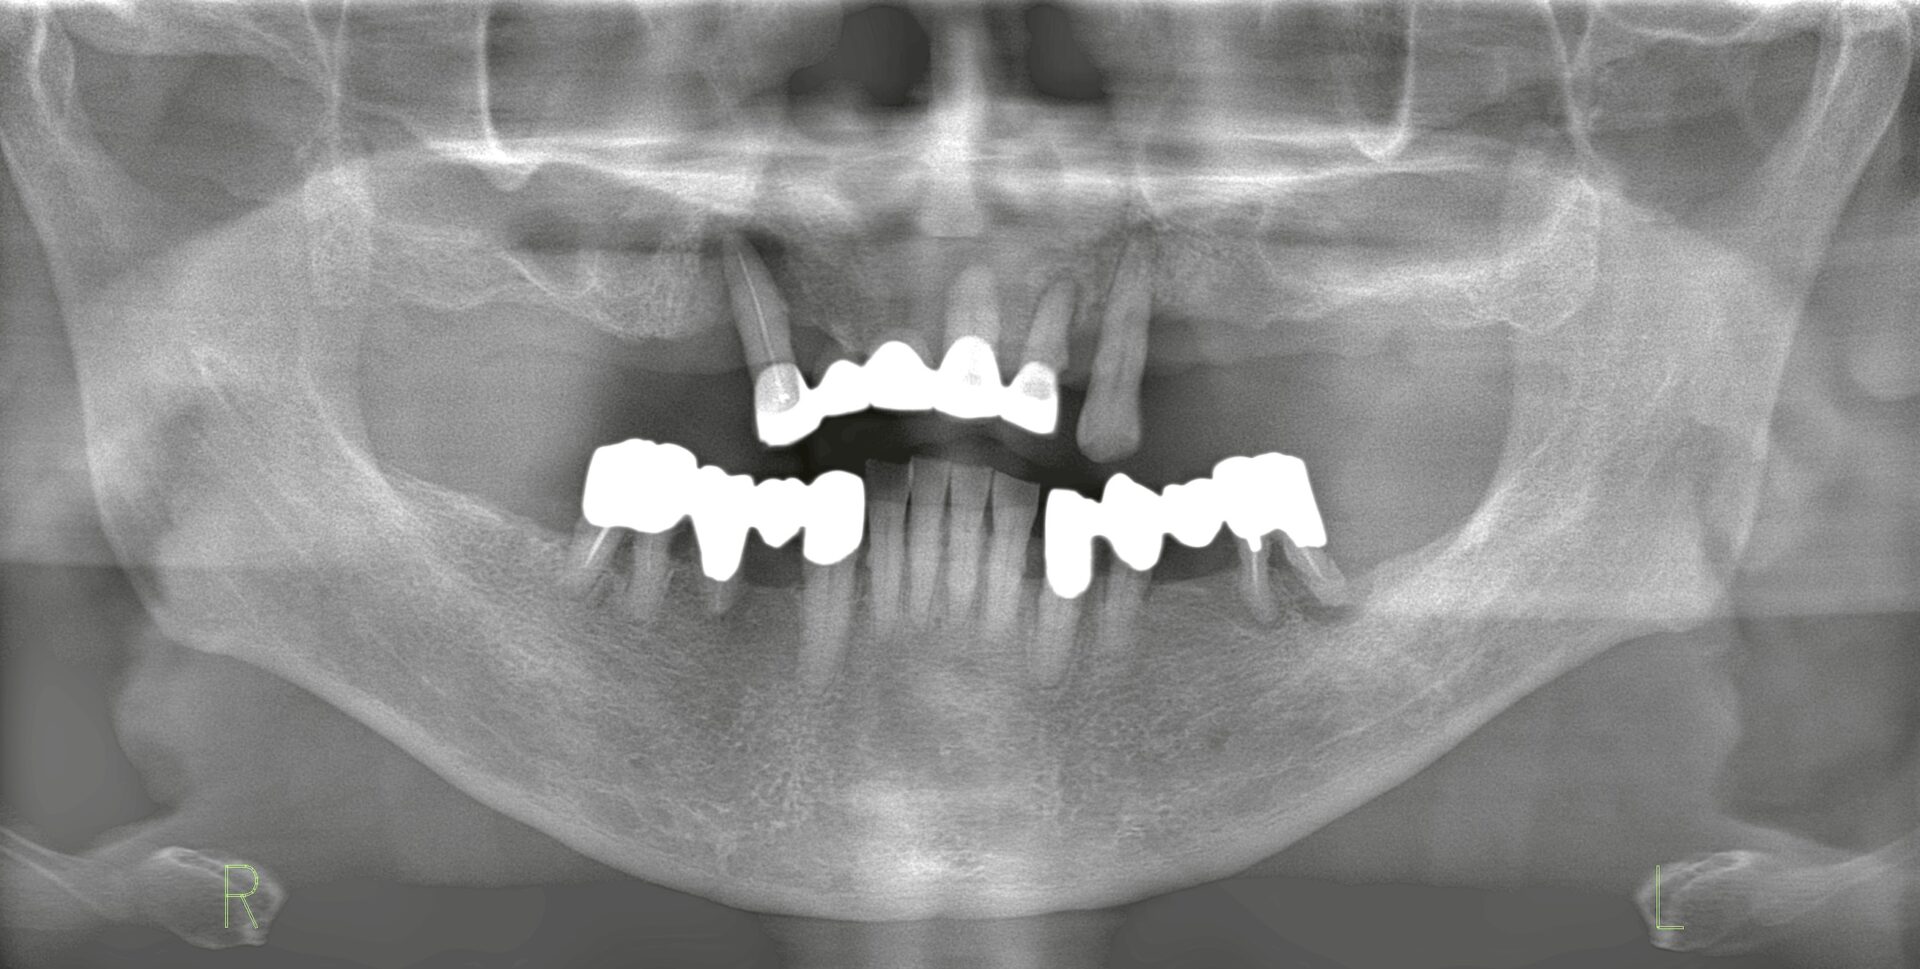

オールオン6による固定式ブリッジ

1. 初期治療(Day 0) ・インプラントを6本埋入。 ・そのうち5本で即時荷重による固定式の仮歯を装着。 2. 3ヶ月後 ・仮歯の交換を実施。咬合や形態を調整し、安定した機能と審美性を維持。 3. 6ヶ月後 ・骨造成部位の二次オペを実施。 ・最終補綴としてジルコニアベースのフルアーチブリッジを装着。長期的な耐久性と審美性を確保。

| Outcome (治療結果・QOLの変化) |

* 仮歯の段階から義歯特有の違和感が消失し、咀嚼機能は著しく改善。 * 食事や会話に対するストレスが軽減され、QOLは治療初期から劇的に向上。 * 最終的なジルコニアベースの補綴物は、高い強度と自然な審美性を兼ね備え、長期的な機能維持を見込める結果となりました。 |